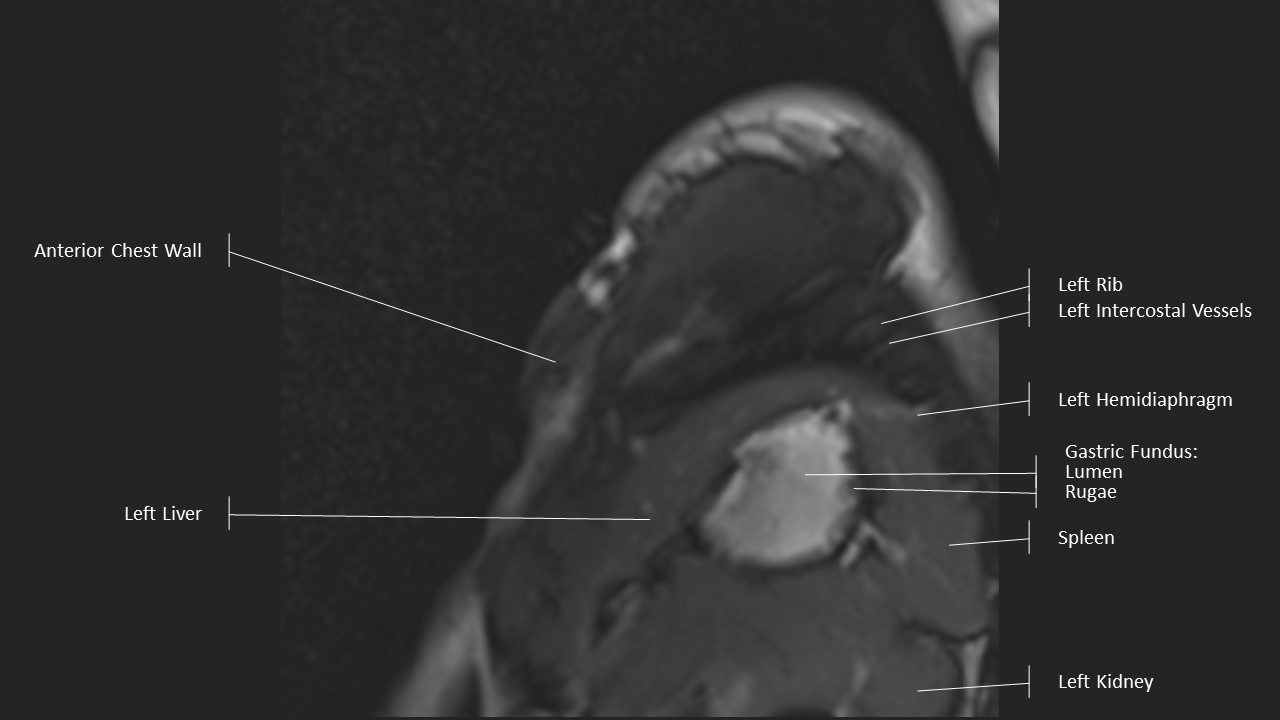

Short Axis Series